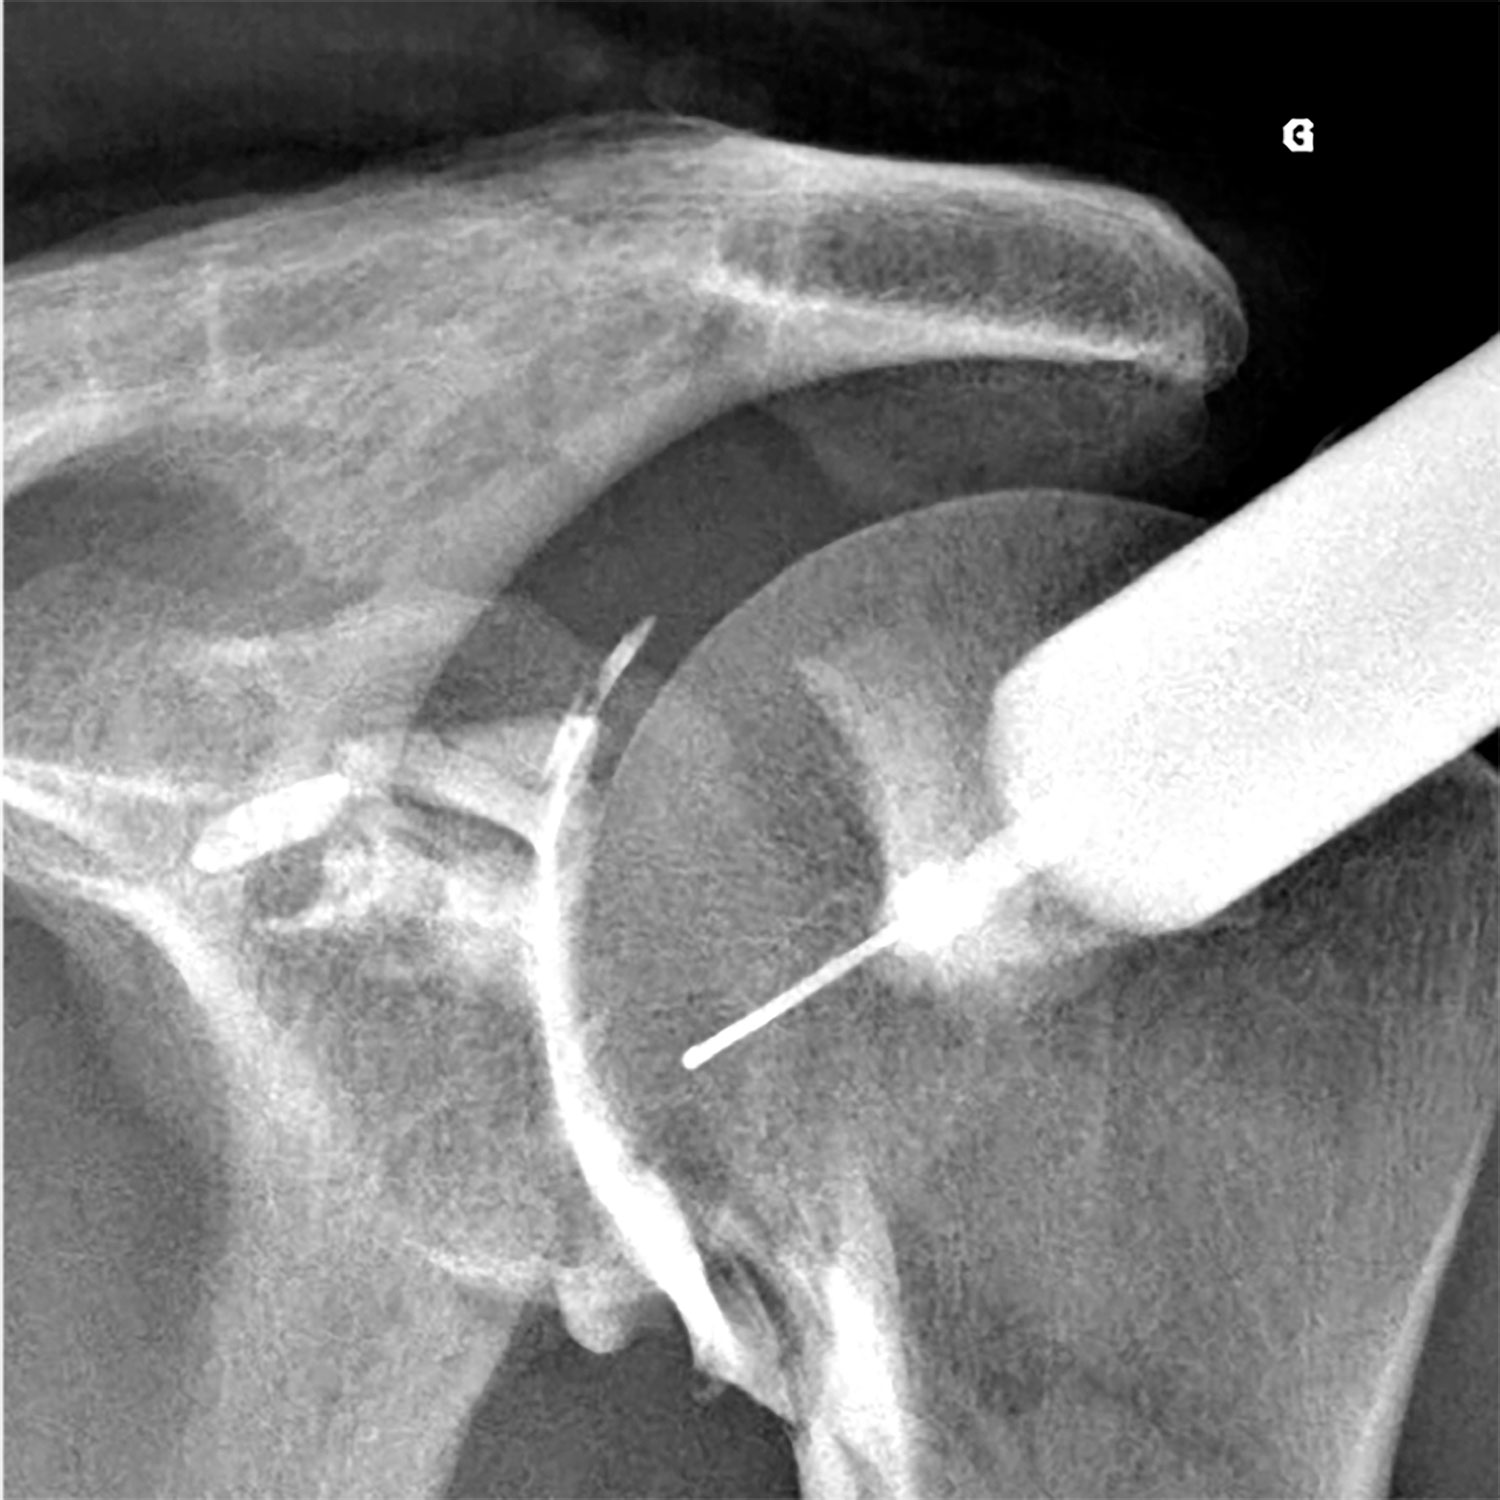

Un grand nombre d'infiltrations s'effectuent sous guidage radioscopique. Pour ces gestes, il est souvent nécessaire d'utiliser un produit de contraste iodé pour vérifier la bonne injection du produit anti-inflammatoire au niveau de la zone souhaitée. Ces infiltrations concernent souvent la colonne vertébrale, mais également les articulations périphériques (épaule, coude, poignet, main, hanche, genou, cheville, pied...).